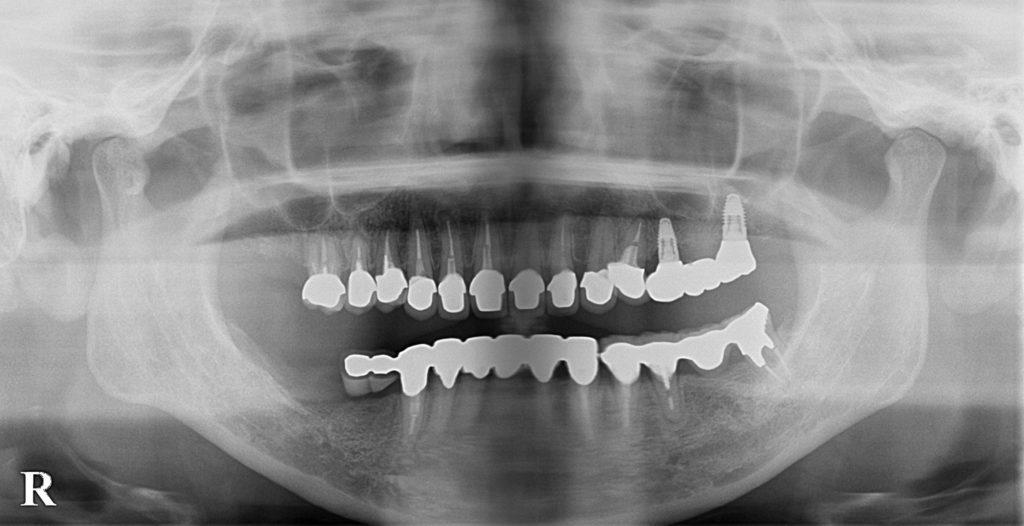

| 診断名 | 臼歯部欠損および全顎的咬合崩壊 |

| 治療方法 | 当初は他院でインプラトができたいと言われた部分(右下)の骨造成処置後インプラト埋入手術を行なった。元々全てセラミックが入っていたが、全体的なバランス(咬合平面、咬合高径)、や歯の色に改善の余地があったため、患者との話し合いの上、可撤性のマウスピースでのトライ→接着性のトライ→セラミックへの置き換えを行なった(デジタルにて)。CADIAXにて術前、術中での顎運動の評価も行なった。 |